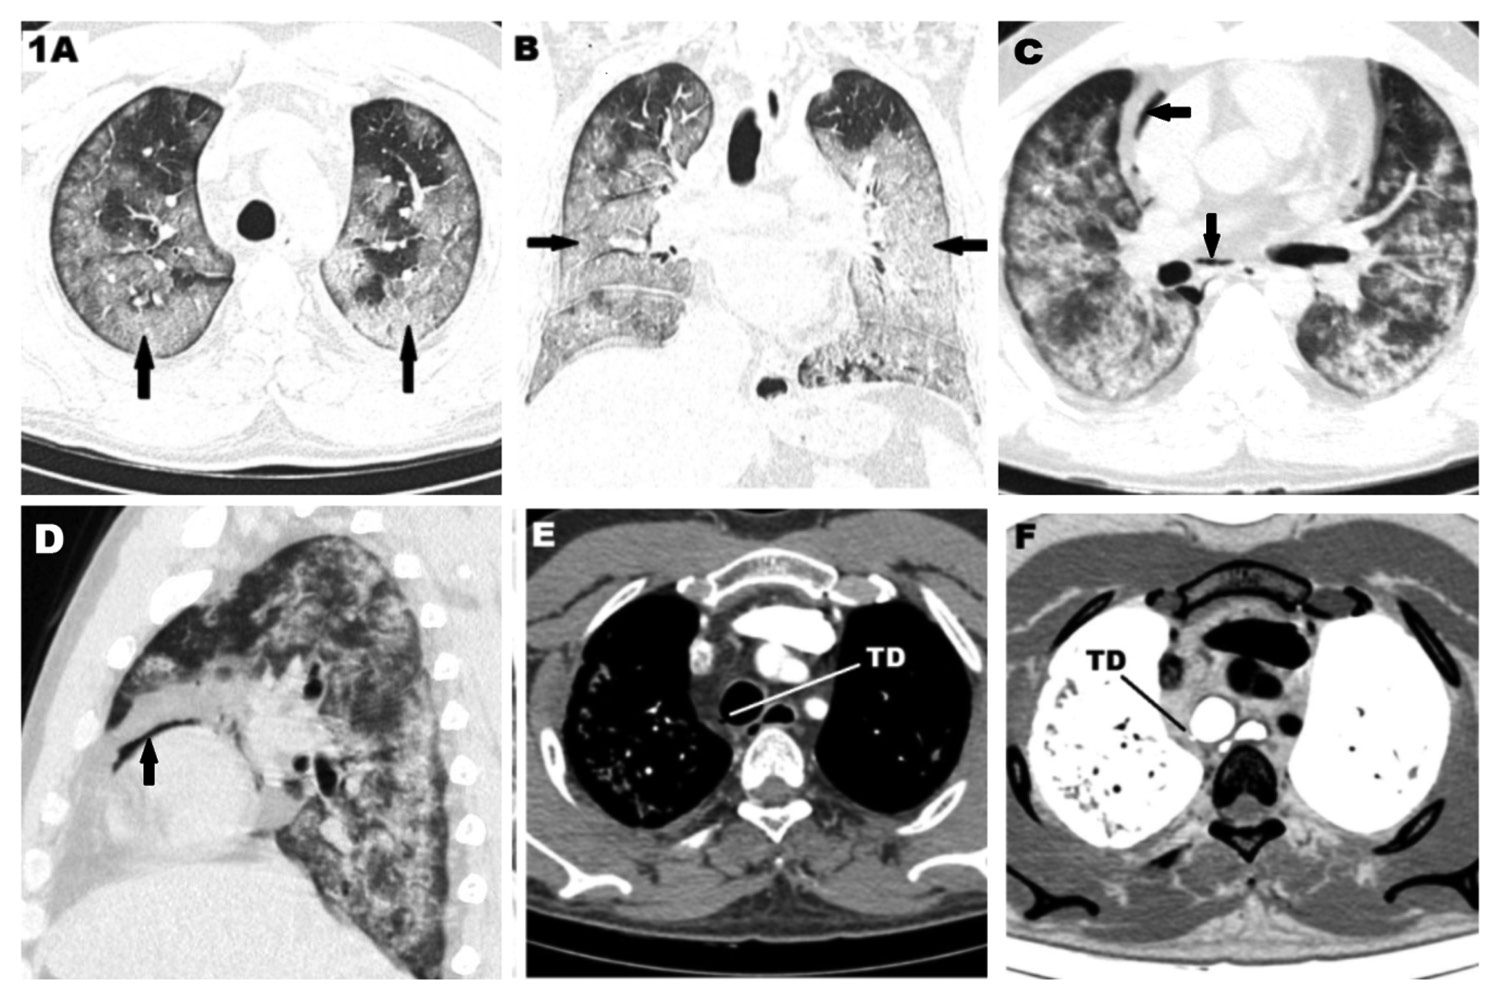

50-year-old man presented with fever, cough and dyspnoea for 3 days. He was RT-PCR positive for SARS-CoV-2. CT thorax with thin sections was done which showed extensive confluent ground glassing with interlobular septal thickening diffusely involving bilateral lung with patchy area of sparing in bilateral apices (Fig. 1 A-B). There was also sparing of immediate subpleural lung in most areas. He had a protracted course in the hospital with persistent hypoxia requiring non-invasive ventilation for 7 days. A CT pulmonary angiogram was done to rule out pulmonary embolism in view of persistent sinus tachycardia. There was no evidence of pulmonary embolism. Lung involvement was similar to the initial study (Fig. 1 C-D). A small focal outpouching was noted from the right posterolateral wall of trachea at the level of D4 vertebra indicating tracheal diverticulum in both conventional and inverted CT imaging along with scattered foci of mediastinal air (Fig. 1 C-F). On reviewing the previously done images there was no evidence of tracheal diverticulum even on the thin cuts (1 mm).

Figure 1. CT scan of a 50-year-old male, RT- PCR positive SARS-CoV-2 patient showing. A. Axial HRCT scan showing multifocal ground glassings in both lung fields typical of covid 19 lesions (arrows). B. Coronal HRCT scan showing extensive involvement in both lungs (arrows). C&D. Axial and sagittal CT scan showing pneumomediastinum (arrows) along with lung lesions after non-invasive ventilation. E&F. showing the tracheal diverticulum (TD) in axial mediastinal window and axial inverted CT images respectively.